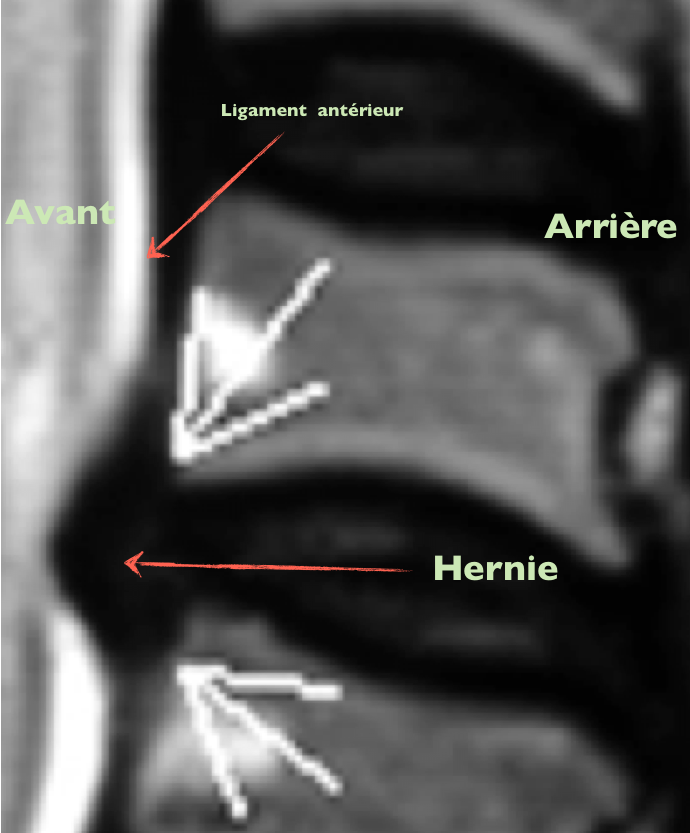

Autre image

Cette personne ne se plaint pas , car la hernie est en avant et déforme le ligament antérieur qui n’est pas innervé = découverte fortuite !